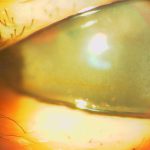

帯状角膜変性(症)は角膜の表層のボーマン膜にカルシウムが沈着して,視力低下,異物感を呈します.病因として若年性関節リウマチなどの慢性前部ぶどう膜炎,角膜の炎症,高カルシウム血症を伴う副甲状腺機能亢進症,サルコイドーシス,腎不全などがあります. 治療は視力低下がみられる場合はEDTA溶液を用いた外科的除去,エキシマレーザーによる切除があります.当院ではEDTA溶液を用いた外科的除去を行っています.下の写真は当院でのEDTAを用いた外科的除去の術前術後です.

症例1